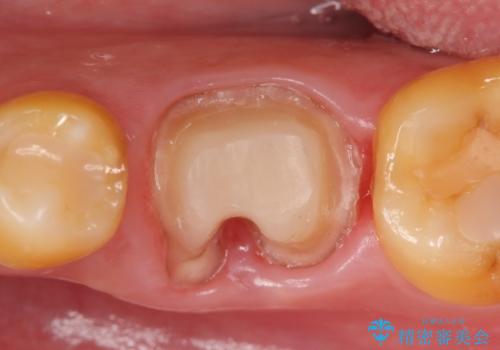

検査の結果、根尖病変が大きくポケットも 10mm 以上ありましたが、マイクロ(顕微鏡)にて精査したところ歯根破折は認められなかったため、再根管治療を行いました。

咬合痛等の症状の緩解、根尖病変の縮小傾向、および深かったポケットが正常値まで改善したことを確認後、オールセラミッククラウンによる補綴を行いました。